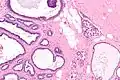

| Micrograph of collagenous spherulosis with the characteristic histomorphology - intratubular eosinophilic material with a spoke-like arrangement. H&E stain. | |

Collagenous spherulosis is characterized by a tubular/cribriform architecture with intratubular eosinophilic material that classically is arranged like the spokes of a wheel ("radial spikes"). There is usually no mitotic activity, and two cells populations (epithelial & myoepithelial) are present, like in benign breast glands.

The lesions are typically small (less than 50 spherules per lesion, less than 100 micrometers in size) and may be multifocal.